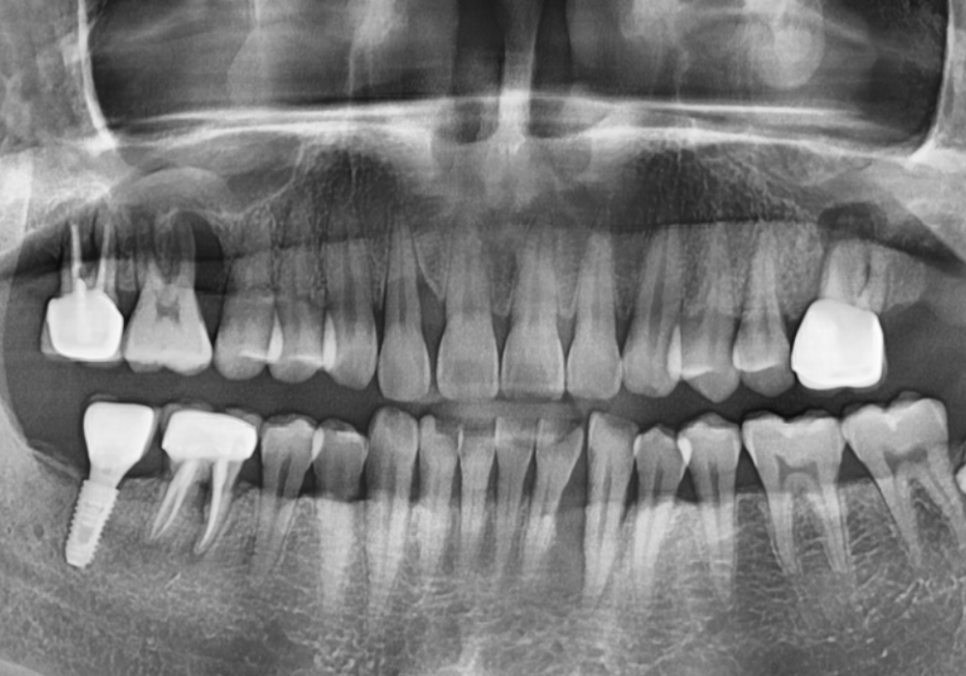

자, 이제 아까 말씀드린

#17 치아의 비밀을 풀기 위해

3D CT 사진을 확인해 보겠습니다.

CT로 확인해 보니 뒷니(#17) 역시

뼈가 이만큼이나 녹아 있었습니다.

240327

앞에 치아와 비교해도 손색없을 정도로

뼈가 많이 사라진 상태였죠.

분명 파노라마 사진에서는

괜찮아 보였는데,

왜 CT에서는 이렇게 뼈가 녹은 게

확실히 보일까요?

그 이유는 파노라마는 1차원적인 평면 사진이라

상이 하나로 겹쳐 보일 수 있기 때문입니다.

반면 3D CT는 입체적인 사진이라

치아를 앞뒤 옆으로 돌려볼 수 있어

훨씬 자세하고 정확한 진단이 가능하죠.